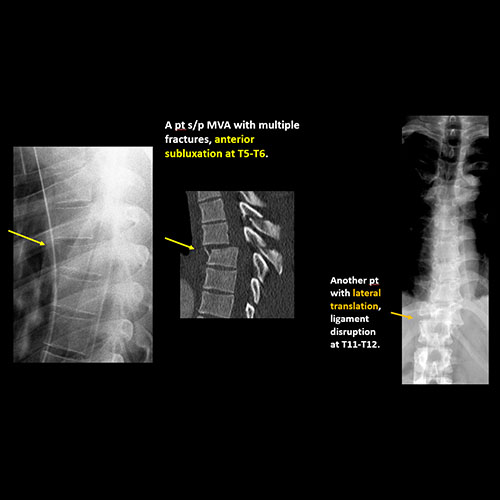

There is an oblique fracture with avulsion through the anterior inferior T9 vertebral body. The posterior elements are intact. There is excessive calcification of the anterior longitudinal ligament and there are continuous osteophytes in a pattern consistent with DISH (Diffuse Idiopathic Skeletal Hyperostosis).

The findings were called to the referring physician and a CT scan is planned.